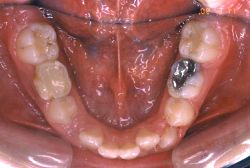

叢生(そうせい)

凸凹な歯並びのことを叢生といいます。矯正歯科に来院する患者様の主訴の中で、最も多いのが「配列の凸凹を真っ直ぐにしたい」というものです。歯の大きさと顎の大きさの調和がとれていないことが原因です。

凸凹を主体としたケースの場合、当院の平均治療期間は18ヶ月ですので、このケースは少し長めに経過しました。理由の一つは凸凹の程度がかなり重症だったと言うことですが、もう一つは、右下第2大臼歯が45度くらい前傾していたため、それを整直化させるために時間を要したと考えています。いずれにしても最終結果は大変よい状態と思います。

治療前は並びが乱れて見た目が悪いというのはもちろん問題ですが、歯科医学的に一番困るのは噛み合わせが悪いという点です。上下の犬歯(3番目の歯)は、上下的に離れた位置にあるため接触することができません。つまり歯としては存在していても、歯としては機能していないということです。